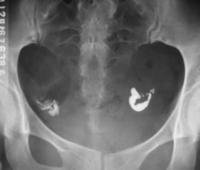

米非司酮異位妊娠是婦科常見急腹症,近年來發病率明顯增加,而且未育患者增多。隨著快速、敏感的β-hCG檢測技術的開展,高解析度的B超套用,使大部分異位妊娠在未破裂前得以診斷,為藥物保守治療提供了條件[1],對仍需保留生育功能的患者,選擇何種藥物及最佳治療方案是一個值得探討的問題。藥物保守治療異位妊娠取得了很大進展,已經成為主要的治療手段[2],其優點是它既能殺死胚胎組織,又不破壞輸卵管組織,從而保持輸卵管通暢。目前,國內外關於異位妊娠保守性藥物治療的報導多數選用氨甲喋呤(MTX)[3,4]。

但氨甲喋呤的化療反應對機體損害大,副作用多。米非司酮問世以來,逐漸被套用於治療異位妊娠,對停經天數少、體內孕激素水平相對較低者,米非司酮抗早孕效果更好。本文對50例異位妊娠患者,以氨甲蝶呤(methotrexate,MTX)為對照,觀察米非司酮(mifepristone,Mif)治療異位妊娠的療效,來探討一種安全、有效、套用方便、副作用少的治療方法。

研究對象及分組,1999年5月~2003年10月異位妊娠入院確診患者50例,年齡最小20歲,最大41歲,平均27歲,停經時間38~65天。診斷依據病史、婦科檢查、血β-hCG及B超檢查,經診刮除外子宮內妊娠。服藥對象:(1)異位妊娠未破裂型或輸卵管妊娠破裂,但出血少;(2)B超檢查輸卵管妊娠包塊直徑6000U/L而患者有藥物保守治療的要求,無米非司酮禁忌證者。(6)肝、腎功能均正常,外周血WBC、RBC、PLT均在正常範圍。